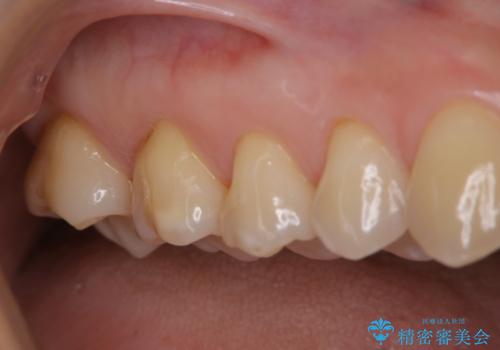

治療中の仮歯もPMTCで白くきれいに